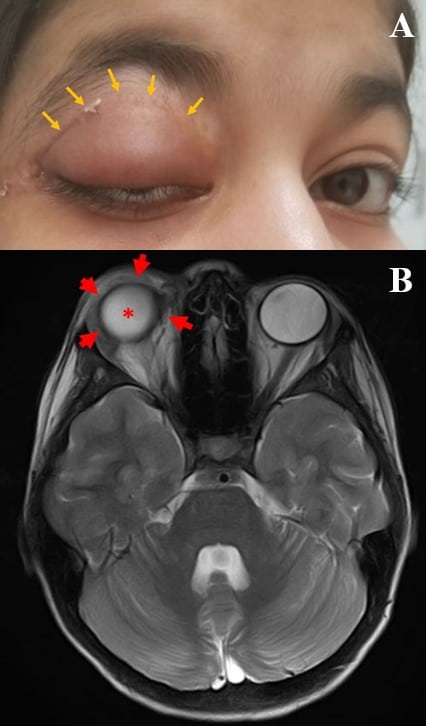

这是一个14岁的女性,最初提出两年后,伴随着无痛的右上眼睑肿胀,如图1a所示(被视为蓝色箭头)。在检查时,右眼睑具有重要的水肿,然而,眼球的完全移动性。在触诊期间,在眼睑下悬垂辛苦,非移动病变。为了确认病变的程度,进行磁共振成像(MRI),其显示出在轨道的边界,中间,内侧和横向(由红色箭头示出)限制的增强病变。病变对潜在的地球仪(显示为星号),然而,具有完整的右视神经和内侧,横向和劣质肌肉[图1B]。